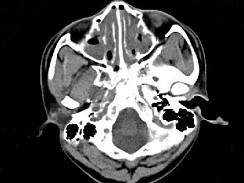

男,14岁,持续性鼻塞、嗅觉减退,流脓涕数年,CT检查如图,最可能的诊断为 ( )

• A.鼻炎及鼻窦炎

• D.鼻及鼻窦息肉

答案: A